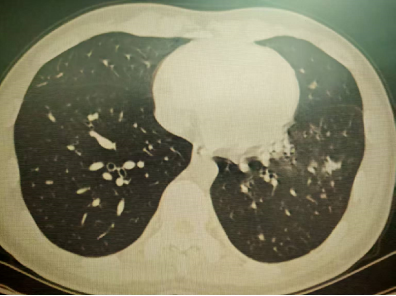

以上是他的胸部CT影像,主要表现为左下肺炎症,片絮影+磨玻璃影。

肺部感染的影像学特征

多发性结节伴快速进展

CT表现为双肺多发实性结节(直径0.5-3cm),结节边缘可见毛刺征及分叶征,特征性表现为短期内体积呈几何级数增长(如1周内增大10倍),需与转移瘤、结核球等鉴别。

混合性密度影与胸腔积液

40%病例出现磨玻璃影与实变影共存,部分结节中央可见液化坏死;30%伴单侧渗出性胸腔积液,积液分析呈渗出性但培养阴性,此表现易误诊为脓胸。

明确诊断后我们给予了正规治疗,患者咳嗽症状迅速缓解,1月后复查胸部CT提示肺部病变大部分吸收。

4月后再次复查胸部CT,提示病灶已经完全吸收。